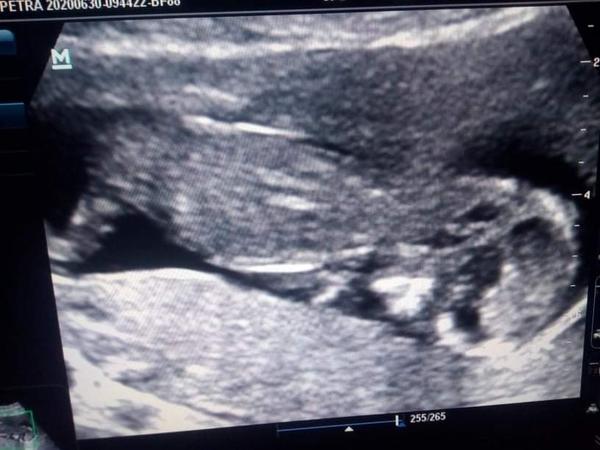

Co myslíte, holka nebo kluk?

Nevím, jestli to co si myslím, že vidím, je pohlavní hrbolek, ale kluk?

Musí se ta fotka otočit právě nám neřekli ale jsem zvědavá babička 😊😊